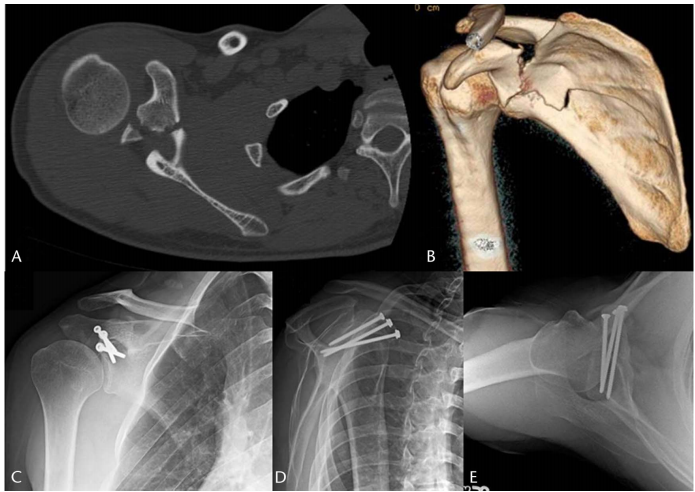

我们倾向于使用长度在 30 到 45 毫米之间的螺钉,并带有 15° 内侧成角和 30-40° 后侧成角,以确保螺钉保持在骨骼内。可以使用另一枚拉力螺钉(图 5)或沿头侧斜面跨越骨折的四分之一管型钢板来补充单枚螺钉,其优点是提供骨折的旋转控制,从而增强对抗上肢牵引力和旋转力的固定。

图 5. A, CT 轴位图像和 (B) 3D 重建显示移位的喙突骨折伴有肩胛骨体部骨折。 C–E, AP、肩胛骨 Y 视图和轴位 X 光片显示使用 3 枚皮质骨拉力螺钉固定后骨折愈合。

关于通过喙突基底的骨折,肩胛上神经因穿过肩胛上切迹的移位骨折而有损伤风险。该切迹位于喙突基底的内侧和邻近处。在复位和固定操作过程中应注意不要损伤肩胛上神经。如果拉力螺钉置入时内侧成角过大,神经可能处于危险之中。